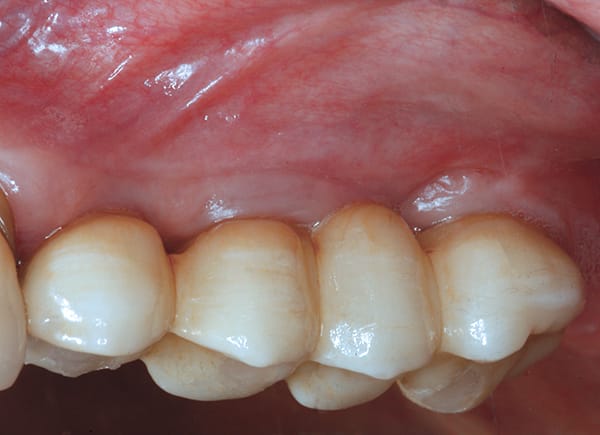

Severe Crestal Atrophy

The patient presented with the posterior mandible showing severe atrophy (Figure 16). The computed tomography (CT) scan showed 3.6 mm and 4.6 mm of available bone height with a failing premolar (Figure 17 and Figure 18). To regain function, the premolar was removed, and two Ultra-Short implants were placed in the molar region and splinted together (Figure 19 through Figure 22).